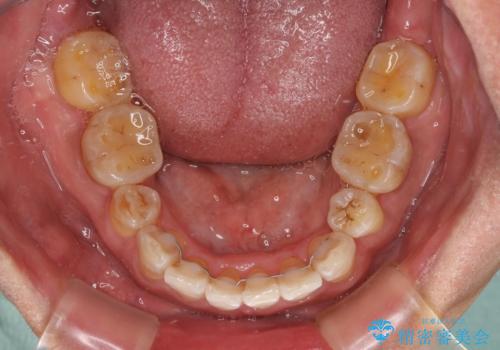

小臼歯の抜歯する部位を選択したことで、安定した咬み合わせとなりましたが、第二小臼歯を抜歯した部分はスペースを閉じるのに長い期間を要しました。

矮小歯であった上顎前歯2本は、矯正治療後にバランスの取れた大きさのオールセラミッククラウンを装着しました。